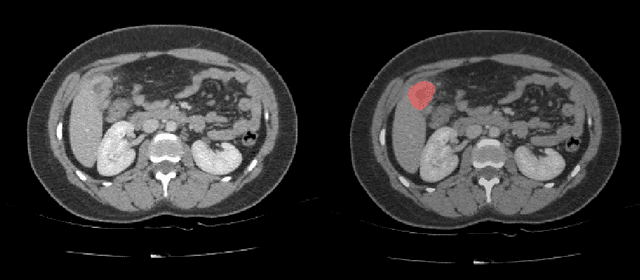

Abstract:Automatic segmentation of hepatic lesions in computed tomography (CT) images is a challenging task to perform due to heterogeneous, diffusive shape of tumors and complex background. To address the problem more and more researchers rely on assistance of deep convolutional neural networks (CNN) with 2D or 3D type architecture that have proven to be effective in a wide range of computer vision tasks, including medical image processing. In this technical report, we carry out research focused on more careful approach to the process of learning rather than on complex architecture of the CNN. We have chosen MICCAI 2017 LiTS dataset for training process and the public 3DIRCADb dataset for validation of our method. The proposed algorithm reached DICE score 78.8% on the 3DIRCADb dataset. The described method was then applied to the 2019 Kidney Tumor Segmentation (KiTS-2019) challenge, where our single submission achieved 96.38% for kidney and 67.38% for tumor Dice scores.